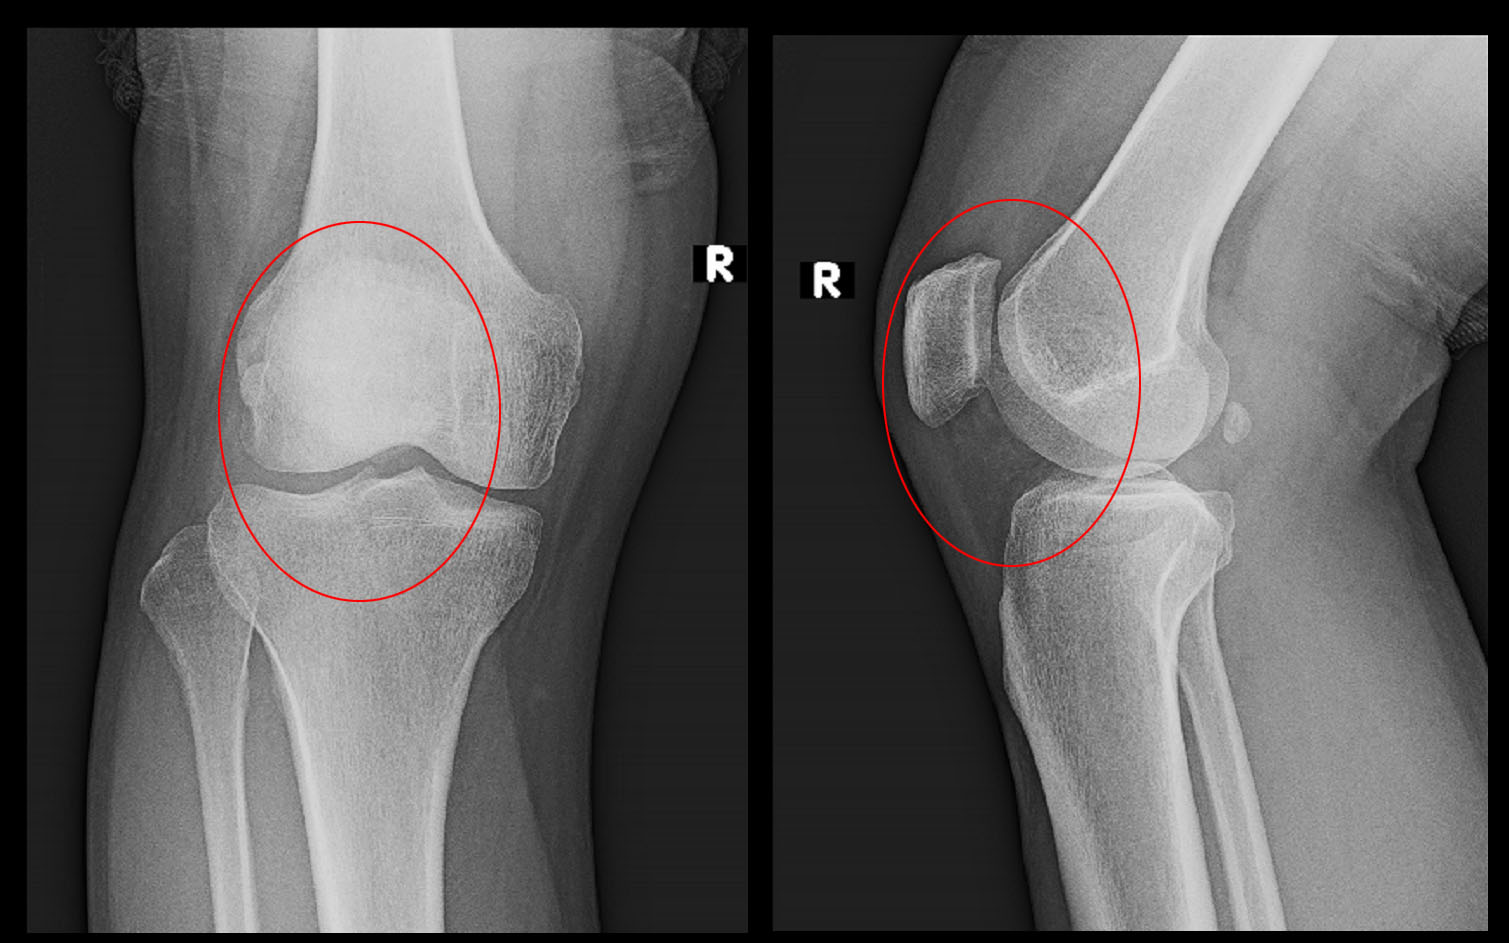

42才の男性です。令和4年3月19日に当院を受診されました。半年前から右膝痛と張る感じが続いているということでの受診でした。階段の昇降でVAS2~4の痛みがあり、子供を抱いての階段昇降はVAS6の痛みであるということでした。半年前まではダイエットのために週に3~4回30分ほど縄跳びをしていたとのことですが、右膝痛で止めたそうです。

42才男 半年続く右膝痛.jpg

レントゲン像の赤丸部分を痛がっていました。レントゲン像では異常は認められません。